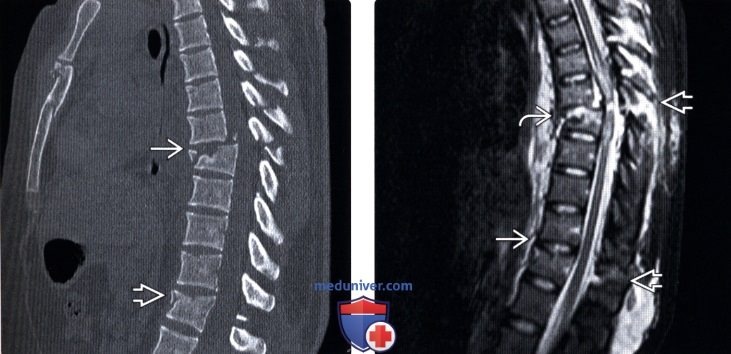

Тот самый ПЕРЕЛОМ ШАНСА относится к разряду флексионно-дистракционных перелом с вовлечением всех позвоночных отделов. При этом, правда, в его классическом варианте происходит сдавление переднего столба (передней трети тела позвонка и пе­редней продольной связки), растяжение среднего столба (задней трети тела позвонка и задней продольной связки) и повреждение заднего столба (дуги позвон­ка, дугоотростчатых суставов, остистого отростка и поперечных отростков).

Ремень безопасности в данном случае работает как точка опоры, в то время как массивное тело человека при столкновении автомобиля с препятствием стремится вперёд и ломается пополам.